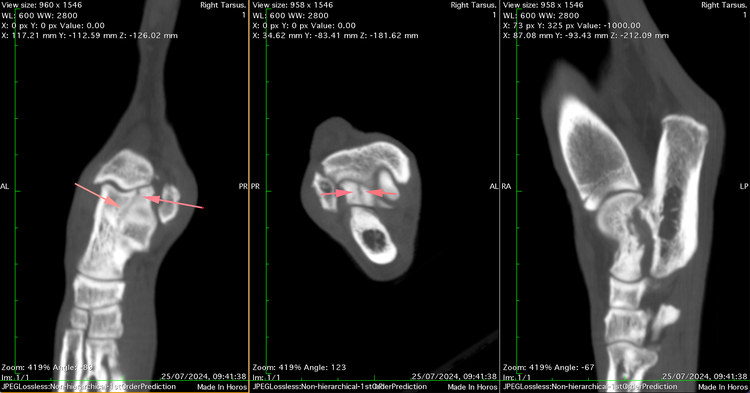

Specialist Orthopaedic surgeon Mark Bush took charge of the case and immediately identified a swollen and painful tarsus. CT imaging uncovered rare and complex fractures—one affecting the sustentaculum tali of the calcaneus and another involving the lateral ridge of the talus, extending into the joint.

CT images of Lola's initial injuries